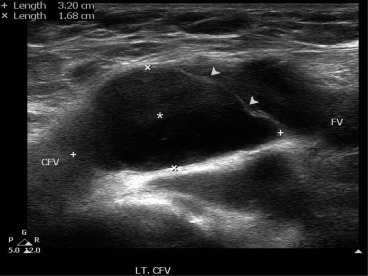

A 50-year-old woman presented with a 1-month history of unexplained edema in the left lower leg. The circumference of the right thigh was 3 cm larger than that of the contralateral side at the mid-thigh level. On the day of admission, her serum D-dimer level was normal (0.26 mcg/mL), but ultrasound examination revealed the presence of an anechoic focal mass, measuring approximately 3.2 cm × 1.7 cm, in the left CFV without compressibility (Fig. 1). A contrast-enhanced computed tomography (CT) scan also showed the presence of an intraluminal low-attenuating mass lesion (2.7 cm × 1.8 cm) involving the left CFV (Fig. 2).

Contrast-enhanced computed tomography demonstrating distension of the left ...

Figure 2.

Contrast-enhanced computed tomography demonstrating distension of the left common femoral vein due to an intraluminal hypoattenuating mass lesion (arrow) attached to the posterior wall. The mass was presumed to be a deep vein thrombus.